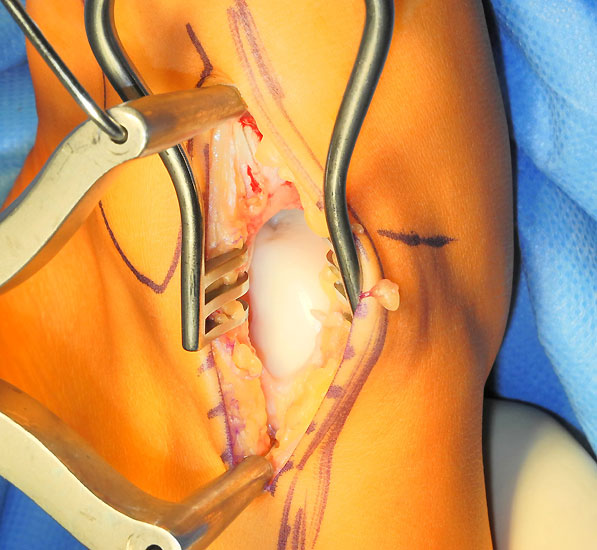

Operationstechnik (Fotos und Video)

Je nach Lage des Knorpeldefektes sind verschiedene Zugänge möglich. Ziel ist einen guten Zugang zum Defekt zu erreichen bei gleichzeitiger Vermeidung einer Innenknöchelosteotomie.

Die Darstellung der weiteren Operationstechnik erfolgt am Beispiel eines medialen Zugangs bei einer Osteochondrosis dissceans mit subchondraler Zyte der medialen Talusschulter (siehe MRT Abbildung 1).

Ist der umliegende Knorpel sehr dick oder liegt nur eine Defektzone mit 1-2 mm Tiefe vor, so kann die Kollagenmatrix auch gedoppelt in Sandwich-Technik implantiert werden. Beide Matrices werden mit der rauhen Oberfläche knochenseitig und der glatten Oberfläche gelenkseitig eingeklebt.